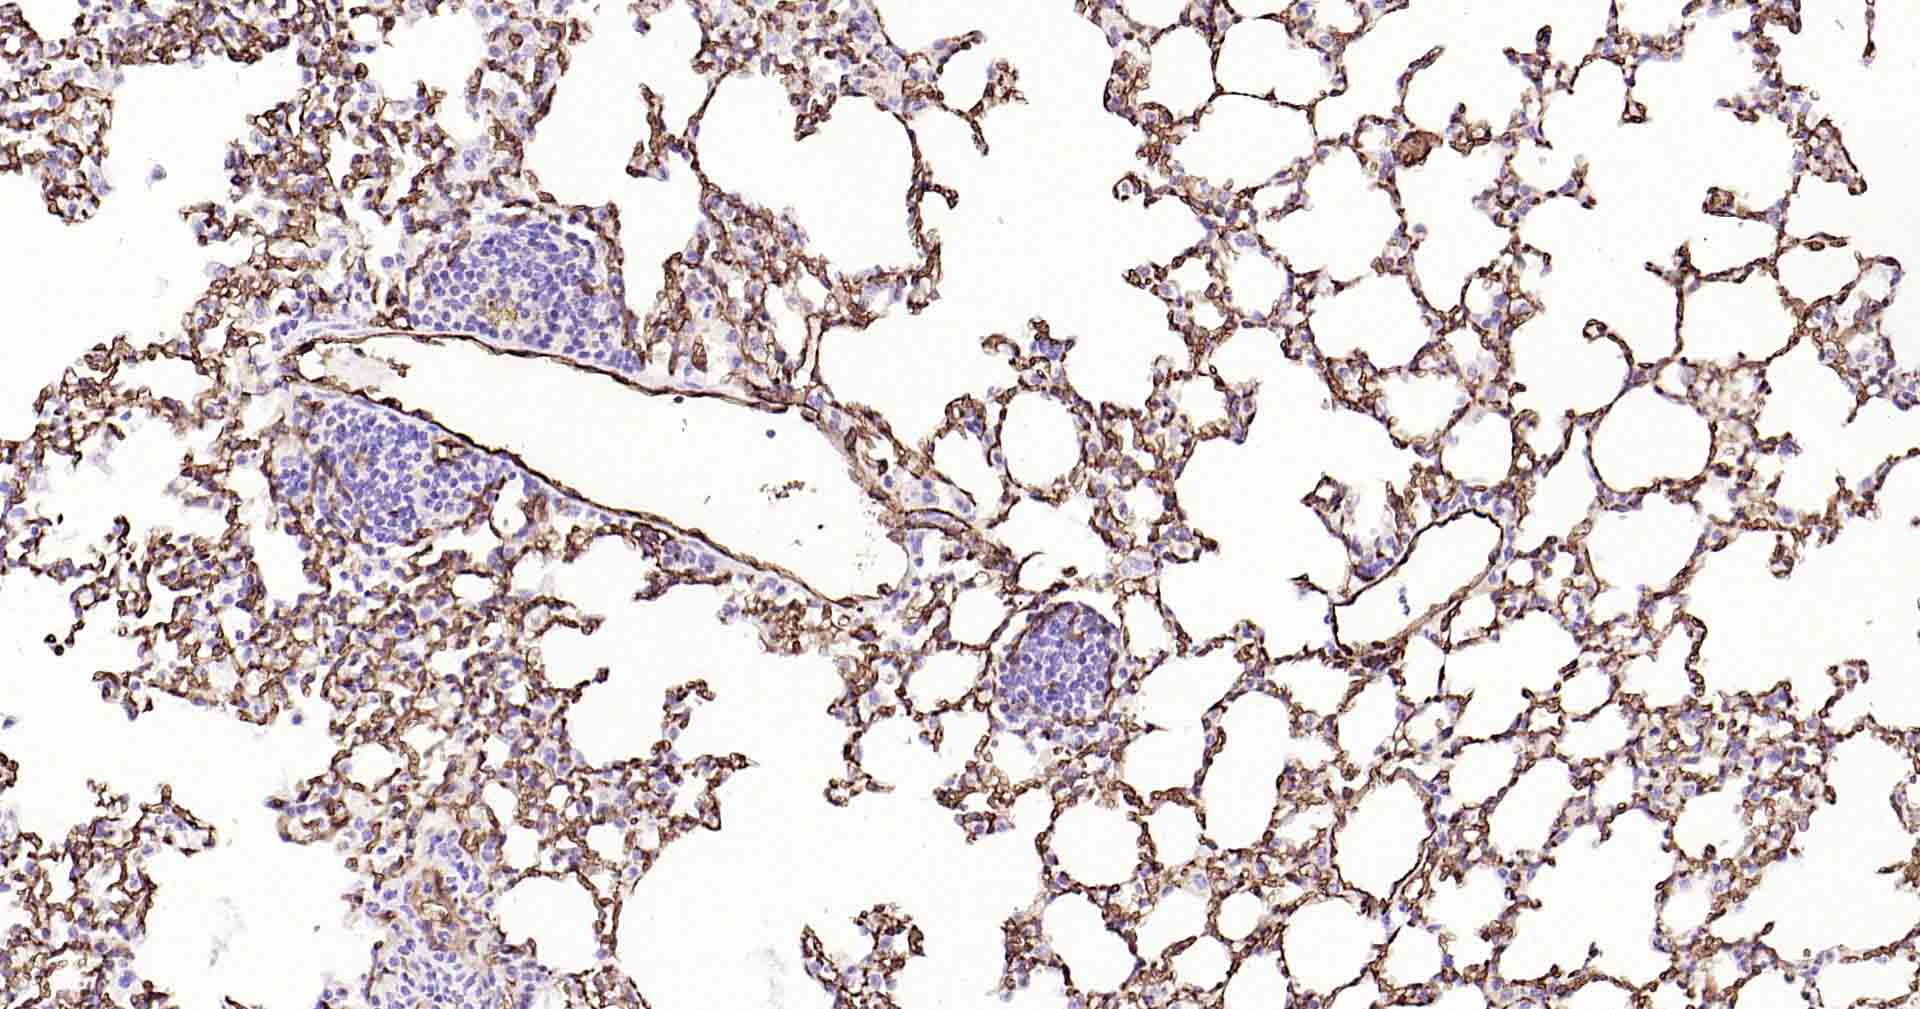

Paraformaldehyde-fixed, paraffin embedded Human Lung; Antigen retrieval by boiling in sodium citrate buffer (pH6.0) for 15 min; Antibody incubation with AQP1 Monoclonal Antibody, Unconjugated(bsm-52909R) at 1:200 overnight at 4°C, followed by conjugation to the SP Kit(Rabbit, SP-0023) and DAB (C-0010) staining.

Paraformaldehyde-fixed, paraffin embedded Rat Lung; Antigen retrieval by boiling in sodium citrate buffer (pH6.0) for 15 min; Antibody incubation with AQP1 Monoclonal Antibody, Unconjugated(bsm-52909R) at 1:200 overnight at 4°C, followed by conjugation to the SP Kit(Rabbit, SP-0023) and DAB (C-0010) staining.

Paraformaldehyde-fixed, paraffin embedded Mouse Lung; Antigen retrieval by boiling in sodium citrate buffer (pH6.0) for 15 min; Antibody incubation with AQP1 Monoclonal Antibody, Unconjugated(bsm-52909R) at 1:200 overnight at 4°C, followed by conjugation to the SP Kit(Rabbit, SP-0023) and DAB (C-0010) staining.